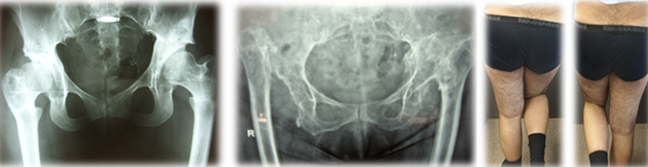

Τα παραμελημένα εξαρθρήματα σε ενήλικα άτομα, όπου η κεφαλή έχει παραμείνει εκτός κοτύλης κι έχει μεταναστεύσει ψηλά, δημιουργώντας μια «ψευδο-κοτύλη» ο πόνος οδηγεί τους ασθενείς σε χειρουργείο. Τα άτομα που πάσχουν από το παραμελημένο είδος του εξαρθρήματος, βαδίζουν μ΄ ένα χαρακτηριστικό «βάδισμα χήνας».

Αυτό οφείλεται στην αδυναμία των μυών του γλουτού (μέσος γλουτιαίος) να συγκρατήσουν την λεκάνη που σε κάθε βήμα βυθίζεται (σημείο Trendelenburg).

Το εξαρθρηματικό σκέλος, λόγω περιορισμένης φόρτισης, είναι συνήθως πιο αδύνατο σε εμφάνιση από το φυσιολογικό και το κόκκαλο πιο στενό-μικρό. Γι΄ αυτό και έχουν κατασκευασθεί ειδικές «προθέσεις» για τα χειρουργεία των εξαρθρηματικών ισχίων.